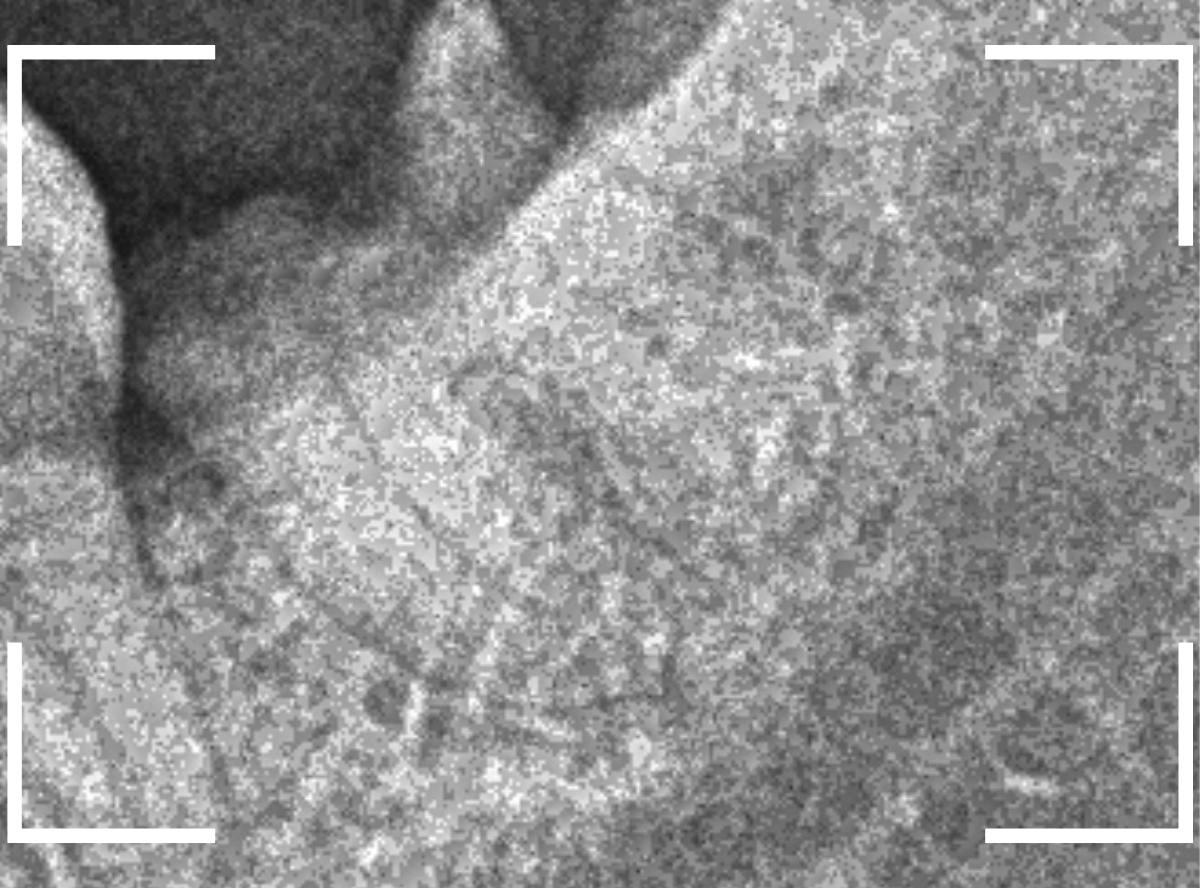

ここでは、比較的簡単なおやしらずの抜歯の例を中心にご紹介します。

このようなおやしらず、あなたはありませんか?